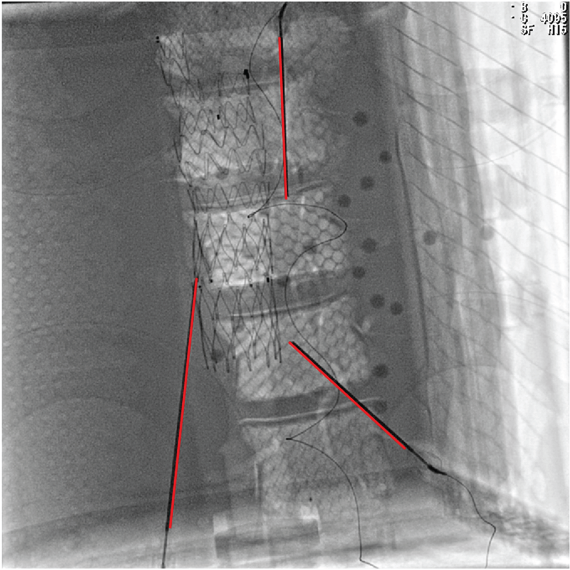

3.4 Phantom experiments

A phantom targeting experiment was conducted to evaluate the accuracy of needle insertion. Fig. 9A shows the experimental setup, including an endoleak phantom, an FG mounting frame, and a Canon Alphenix C-arm (Canon Inc., Tokyo, Japan). Three magnetically tracked needles were inserted into the endoleak phantom. During 2D navigation, the tracked needles (red lines) were projected on the fluoroscopic image, while the actual needles appeared as dark lines. The discrepancies between the two were used to quantify 2D targeting accuracy.

Fig. 9B illustrates the 3D navigation, including 3D reformations, the rendered contrast-enhanced CT volume, and tracked needles. To validate 3D needle insertion accuracy, we acquired a post-insertion non-contrast CT image (Fig. 9C). The inserted needles were clearly visible in three orthogonal views, with the 3D view displaying the inserted needles in silver and the tracked needles in cyan. Needle tip and angle errors were calculated by comparing the tracked needles with their segmented counterparts from the CT image. This process was repeated three times, with a total of nine inserted needles. The overall needle insertion errors were for the tip, and for orientation, as shown in Table 5.